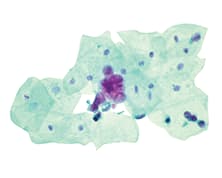

Zetiq, a fully-owned subsidiary of Micromedic Technologies, presents CellDetect®, an innovative staining platform using both color and morphology to discriminate between normal and neoplastic cells.

Applicable to a variety of specimens including histological tissues and cytological smears, CellDetect® highlights suspicious cells in red-purple, therefore enhancing accuracy and increasing throughput.

CellDetect® Bladder cancer kit for the monitoring of bladder cancer recurrence in urine specimens provides high sensitivity, particularly for the detection of low grade tumors. Suitable for both liquid-based and conventional cytology, the technology uses standard lab staining processes and is potentially applicable for digital cytopathology.